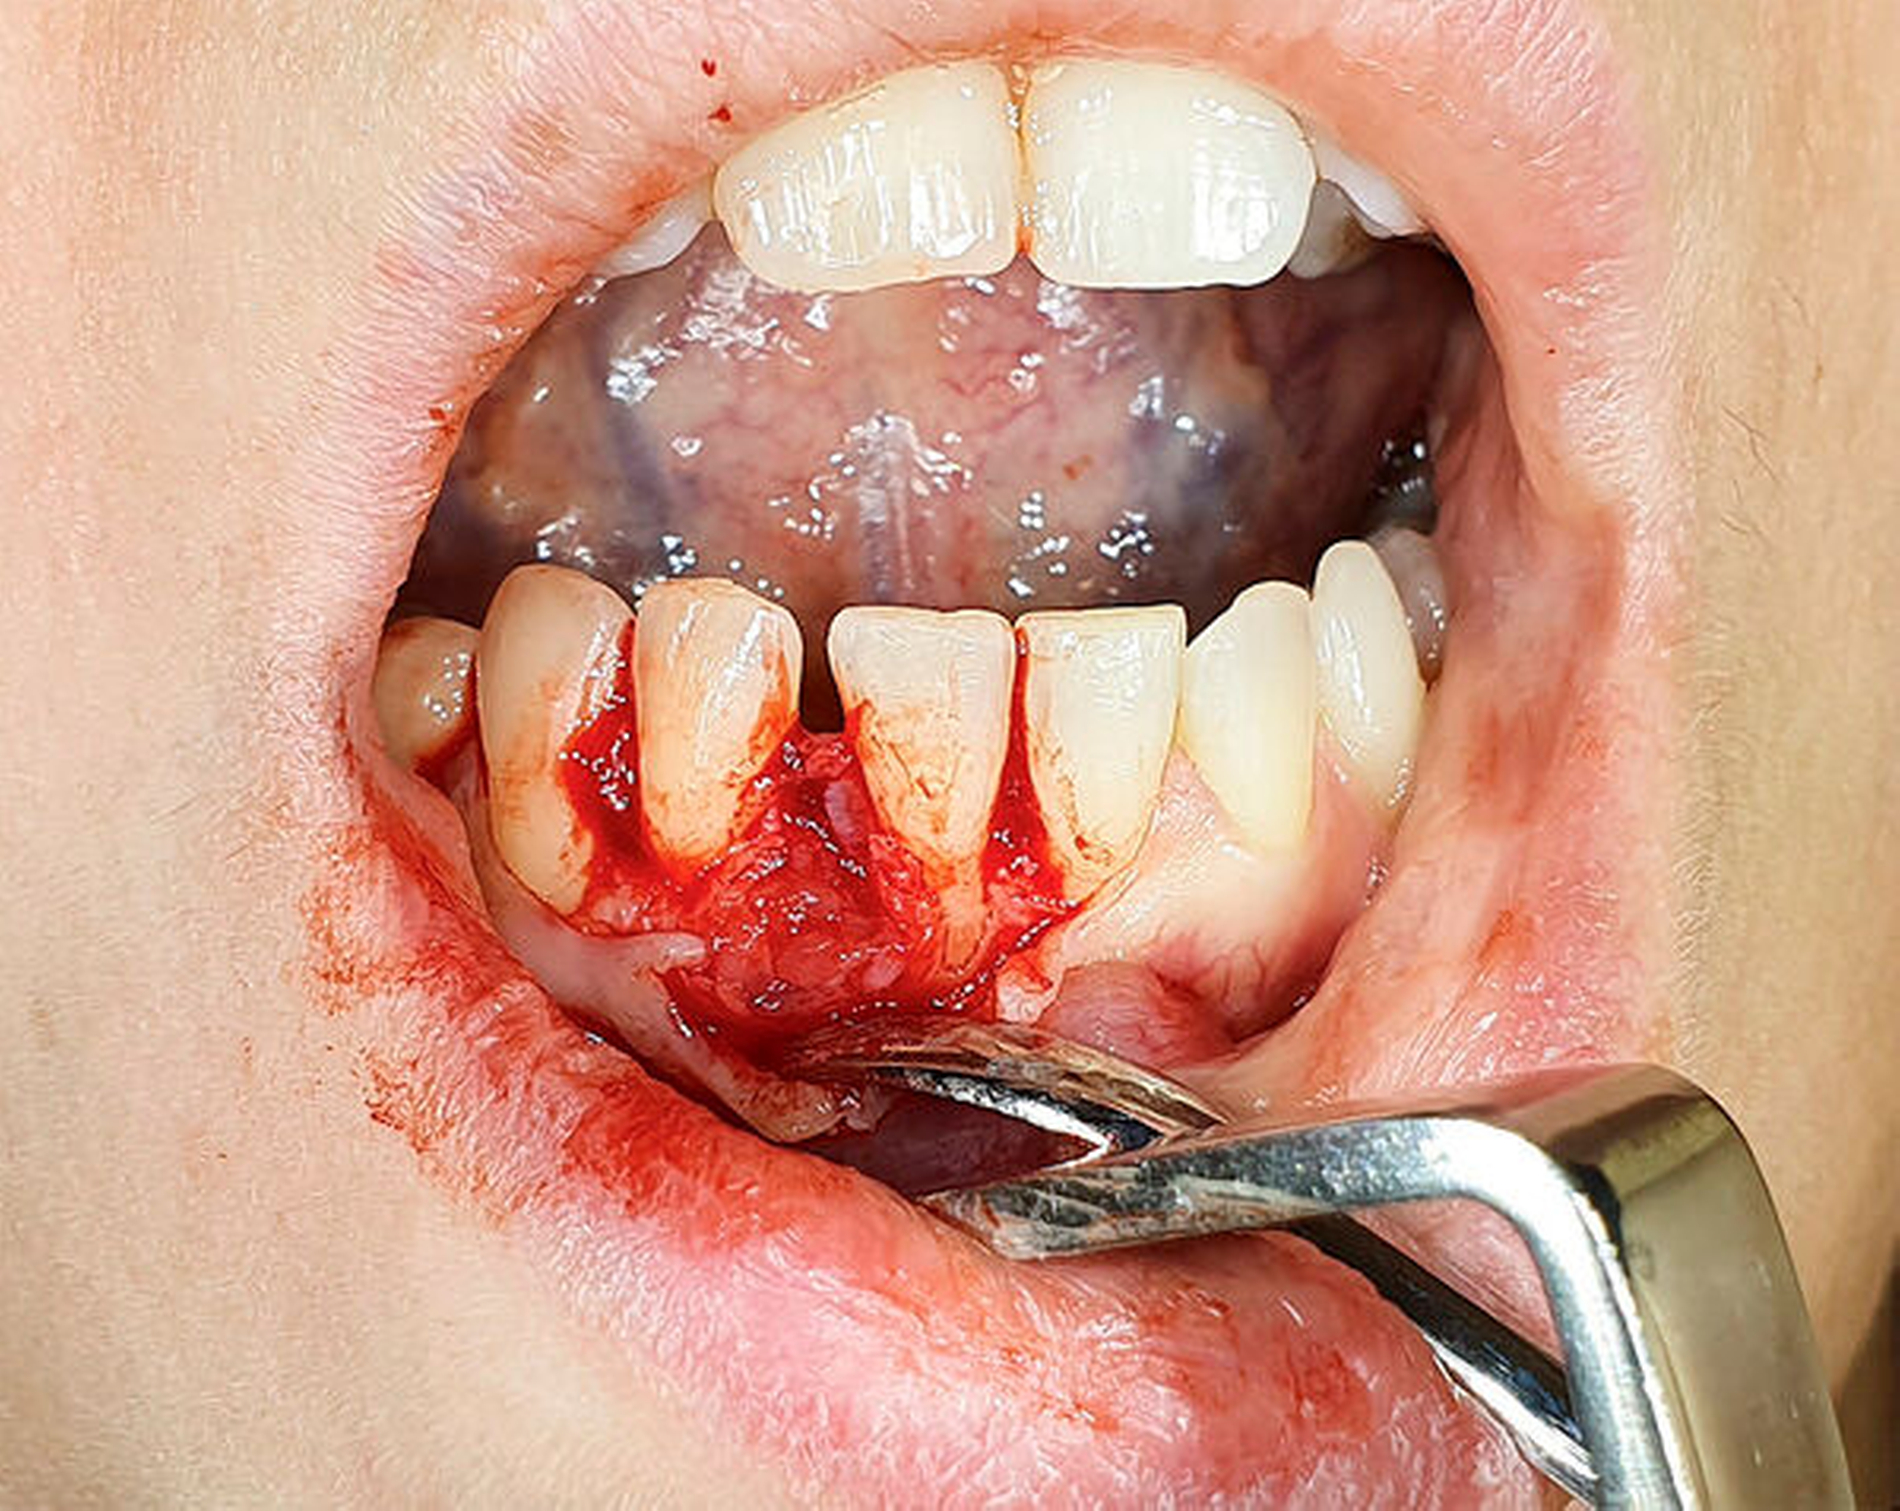

Der Eingriff erfolgte unter Lokalanästhesie. Nach marginaler Schnittführung und Bildung eines Mukoperiostlappens wurde die Raumforde-rung, die nach vestibulär erhaben und partiell von Knochen bedeckt war (Abbildung 2), interdental ersichtlich.

Nach der kompletten Darstellung erfolgte die Resektion in toto (Abbildung 3).

Anschließend wurden der umliegende Knochen und die freiliegenden Wurzelflächen der Zähne 41 und 42 kürettiert (Abbildung 4) und die entstandene Knochenkavität wurde mittels autologem Thrombozytenkonzentrat (Platelet Rich Fribrin – PRF) aufgefüllt.